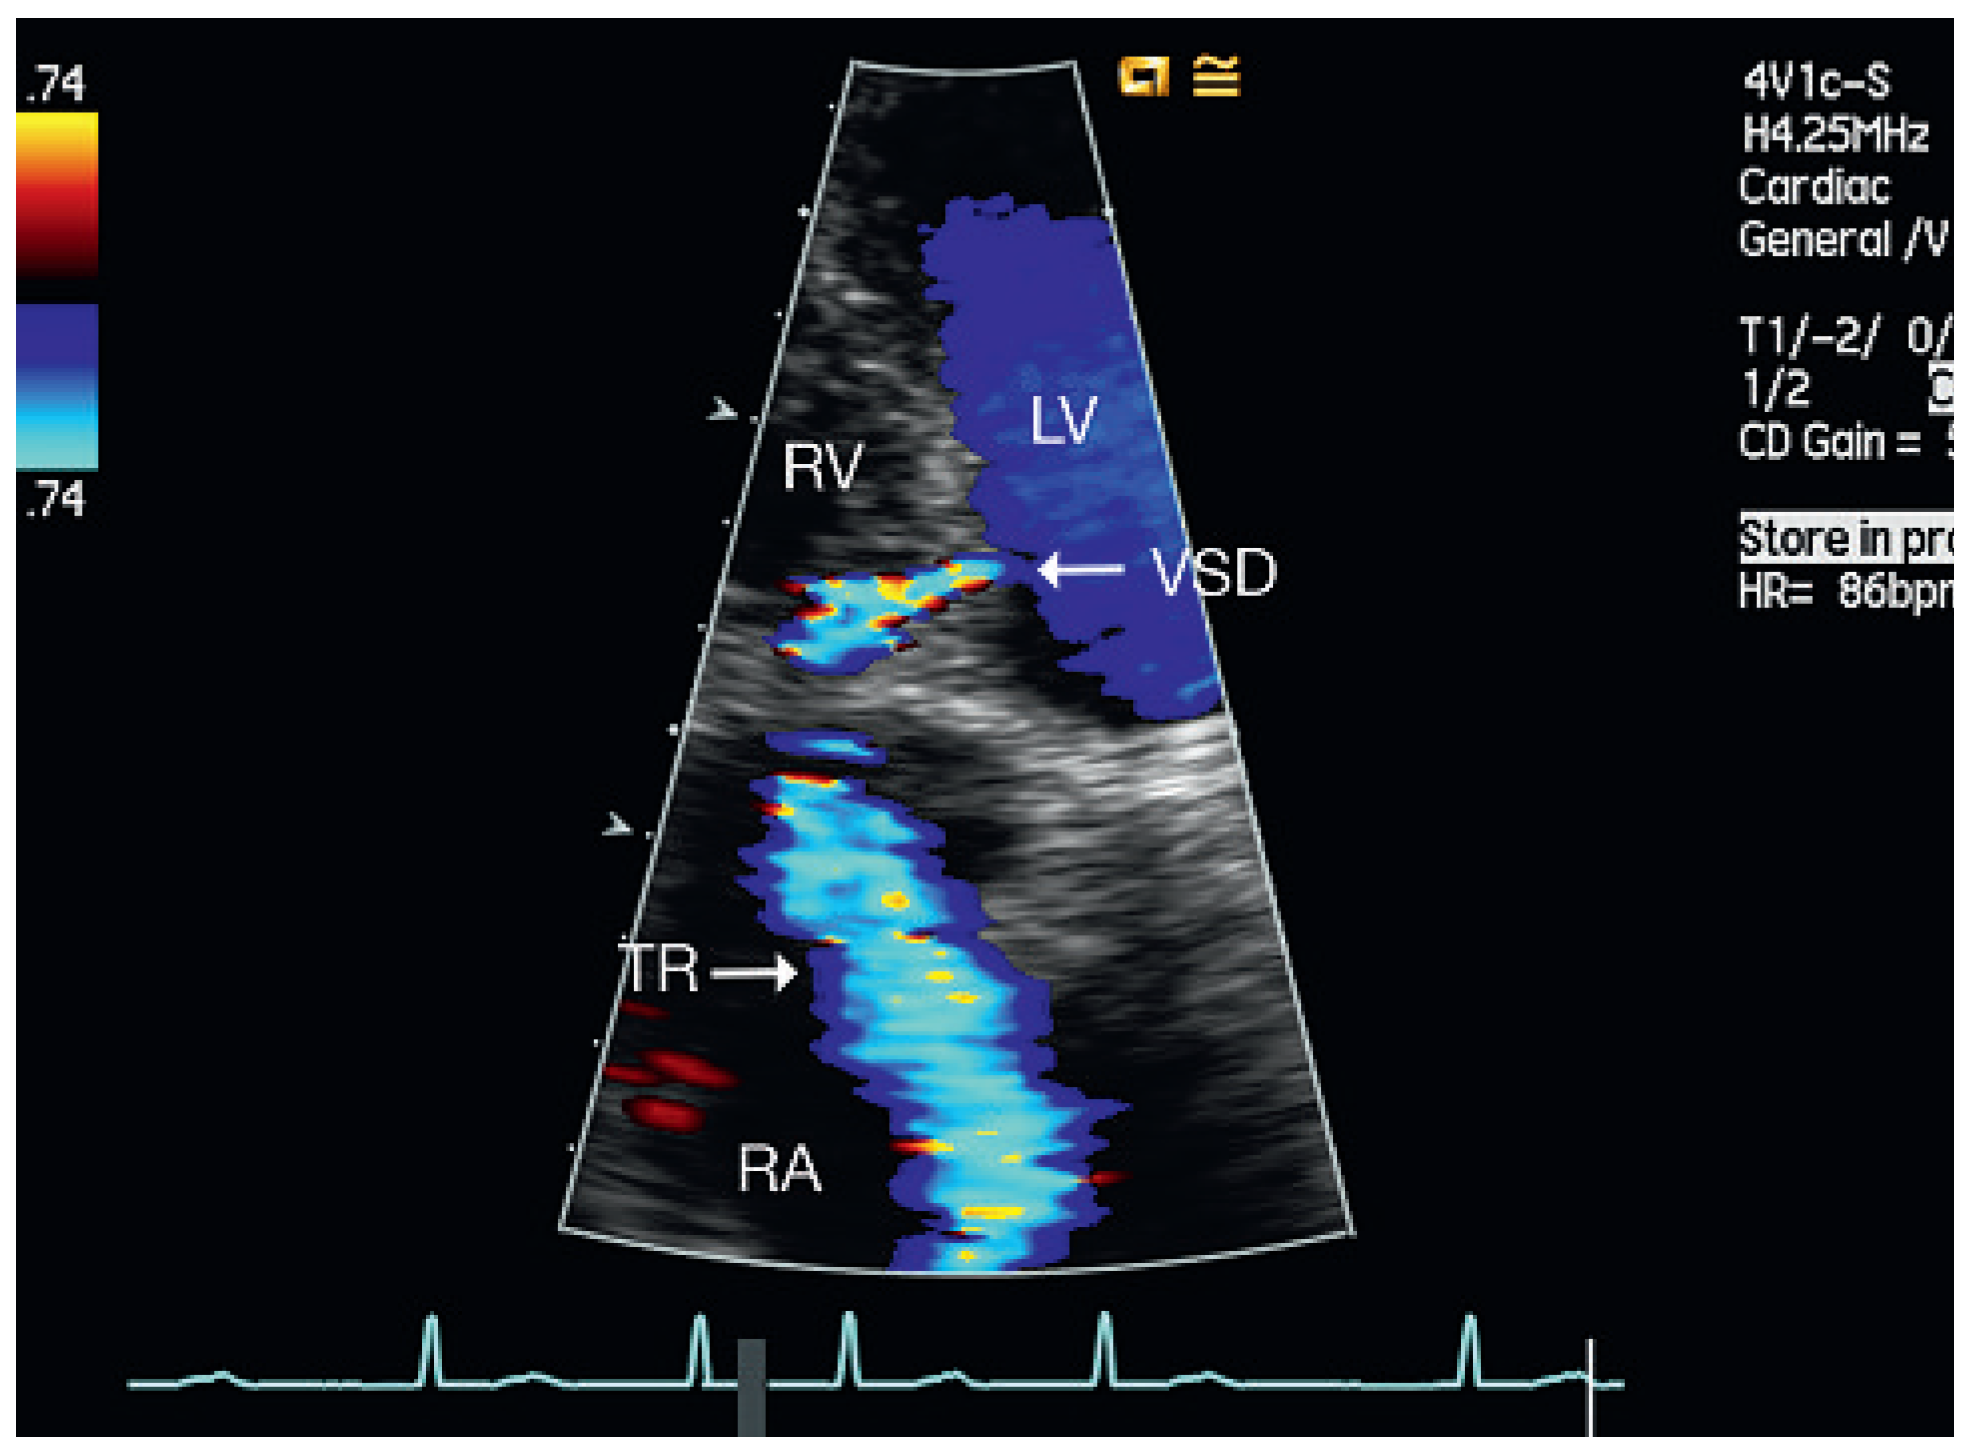

Figure 4.

Patient 3, at admission. Four-chamber view: muscular VSD mid-septal. LV = left ventricle; RA = right atrium; RV = right ventricle; TR = tricuspid regurgitation; VSD = ventricular septal defect.

From September 2007 to December 2008, five patients aged 54–69 years were admitted to our institution for cardiac rehabilitation after surgical cardiac valve replacement (Table 1). Successful replacement of the aortic valve was performed in four of the patients and mitral valve replacement in the other. All patients received mechanical prosthetic valves (ATS medical) and had a history of dyspnoea, fatigue and exercise limitation. Physical examination on admission did not reveal signs of congestion in any of the patients. The admission electrocardiogram showed sinus rhythm or atrial fibrillation (patient 4) and signs of left ventricular hypertrophy in 3 of 5 patients. Doppler echocardiography revealed a restrictive muscular ventricular septal defect (Figure 1, Figure 3, Figure 4, Figure 5 and Figure 6) with Qp/Qs < 1.4 in all of the patients. The function of the prosthetic valves was normal and in one patient (patient 5) systolic pump function was moderately reduced.

Echocardiographic follow-up revealed spontaneous closure of the septal perforation in four of the five patients (Figure 2). In one patient the septal defect persisted for one and a half years after surgery, but he remained asymptomatic without deterioration of left ventricular function or increased pulmonary artery systolic pressure.